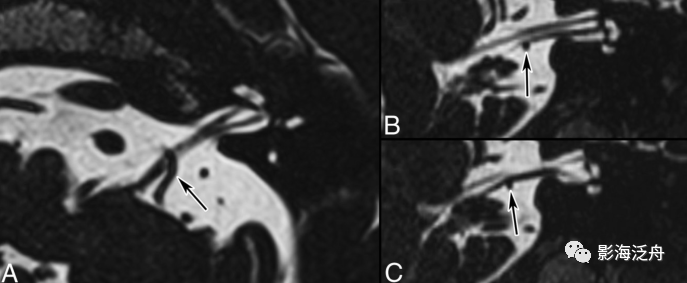

在轴位MR图像上观察并准确辨识出相应的神经和血管,常规的FSE T2WI也可以看到这些颅神经和血管,但不够清晰,尽量还是在更专业的3D重T2WI序列或3D B_FFE序列上观察,如下图↓

T2-TSE3D-RST-TRA成像是重T2成像,脑脊液呈高信号,三叉神经,面听神经和血管在脑脊液的高信号衬托下呈低信号可清晰显示,即使周围很小的血管分支也可能成像。

此外,T2-TSE3D-RST-TRA能对静脉以低信号成像,而且无须造影剂,通过多层面分析可确定压迫血管的来源,与常规磁共振技术相比不仅扫描速度成倍提高,并且通过三维薄层技术弥补对比度和分辨率的损失,获得高分辨率、高信噪比的图像,是检查脑神经和血管成像的最佳技术。